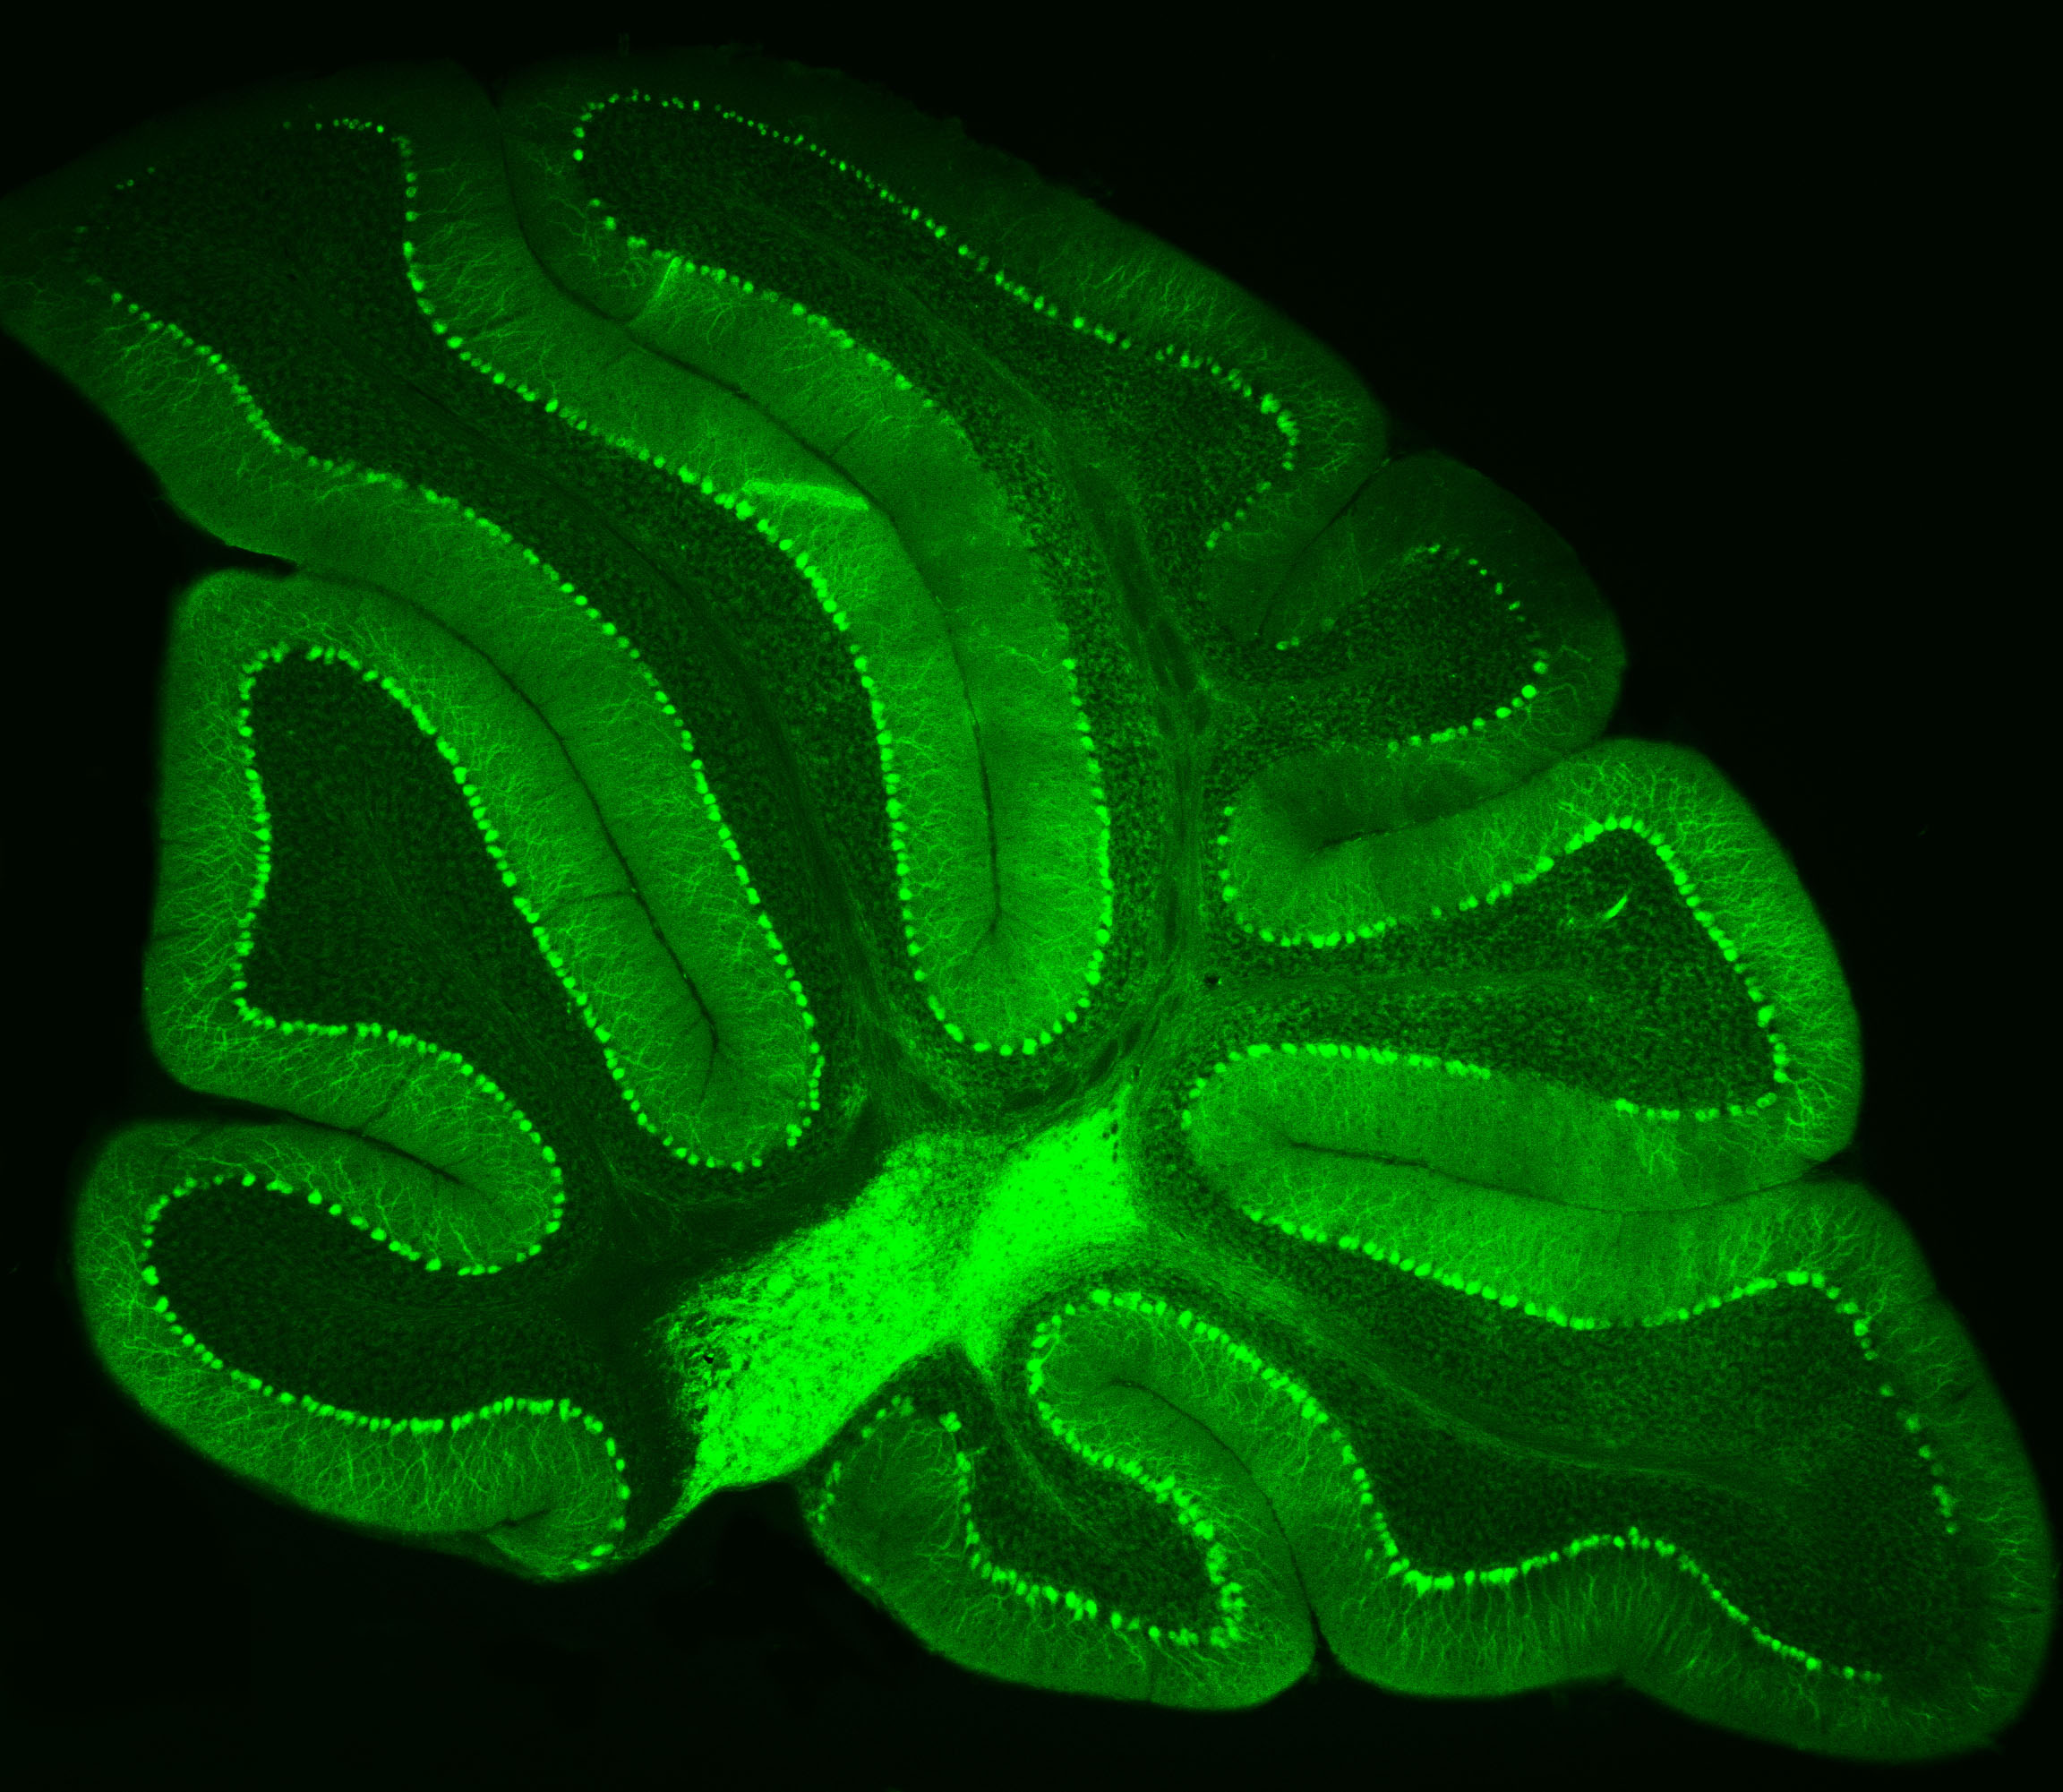

Neurons in Green

Purkinje neurons from an animal model are labeled with green fluorescent protein (GFP), which causes them to glow bright green.

– Credit: Pennington Biomedical

At Pennington Biomedical Research Center, scientists often study the brain by highlighting specific cells so they can be seen more clearly under a microscope. This technique was recently used by Dr. Yanlin He, associate professor and director of the Brain Glycemic and Metabolism Control Laboratory, who is examining Purkinje neurons in the cerebellum.

Purkinje neurons are best known for helping control movement and motor learning, but researchers are discovering they may have other important roles in the body as well, such as controlling energy balance and blood sugar.

By making these neurons glow green, Dr. He and his team can see their complex branching shapes and how they connect within the cerebellum’s neural network.

This technique also allows researchers to perform electrophysiology recordings, which measure the electrical activity of the cells in a laboratory setting. Their work could help scientists better understand how the brain helps regulate metabolism and overall health.